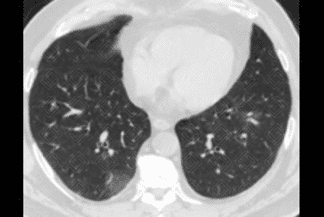

Descrição das figuras 4, 5, 6 e 7: Radiografia e nova tomografia de tórax, realizadas 4 dias após admissão, evidenciando piora dos achados pulmonares. Importante aumento das opacidades em vidro fosco periféricas.

• Diante da evolução desfavorável, pode ocorrer aumento das opacidades em vidro fosco, com surgimento de áreas de consolidação;